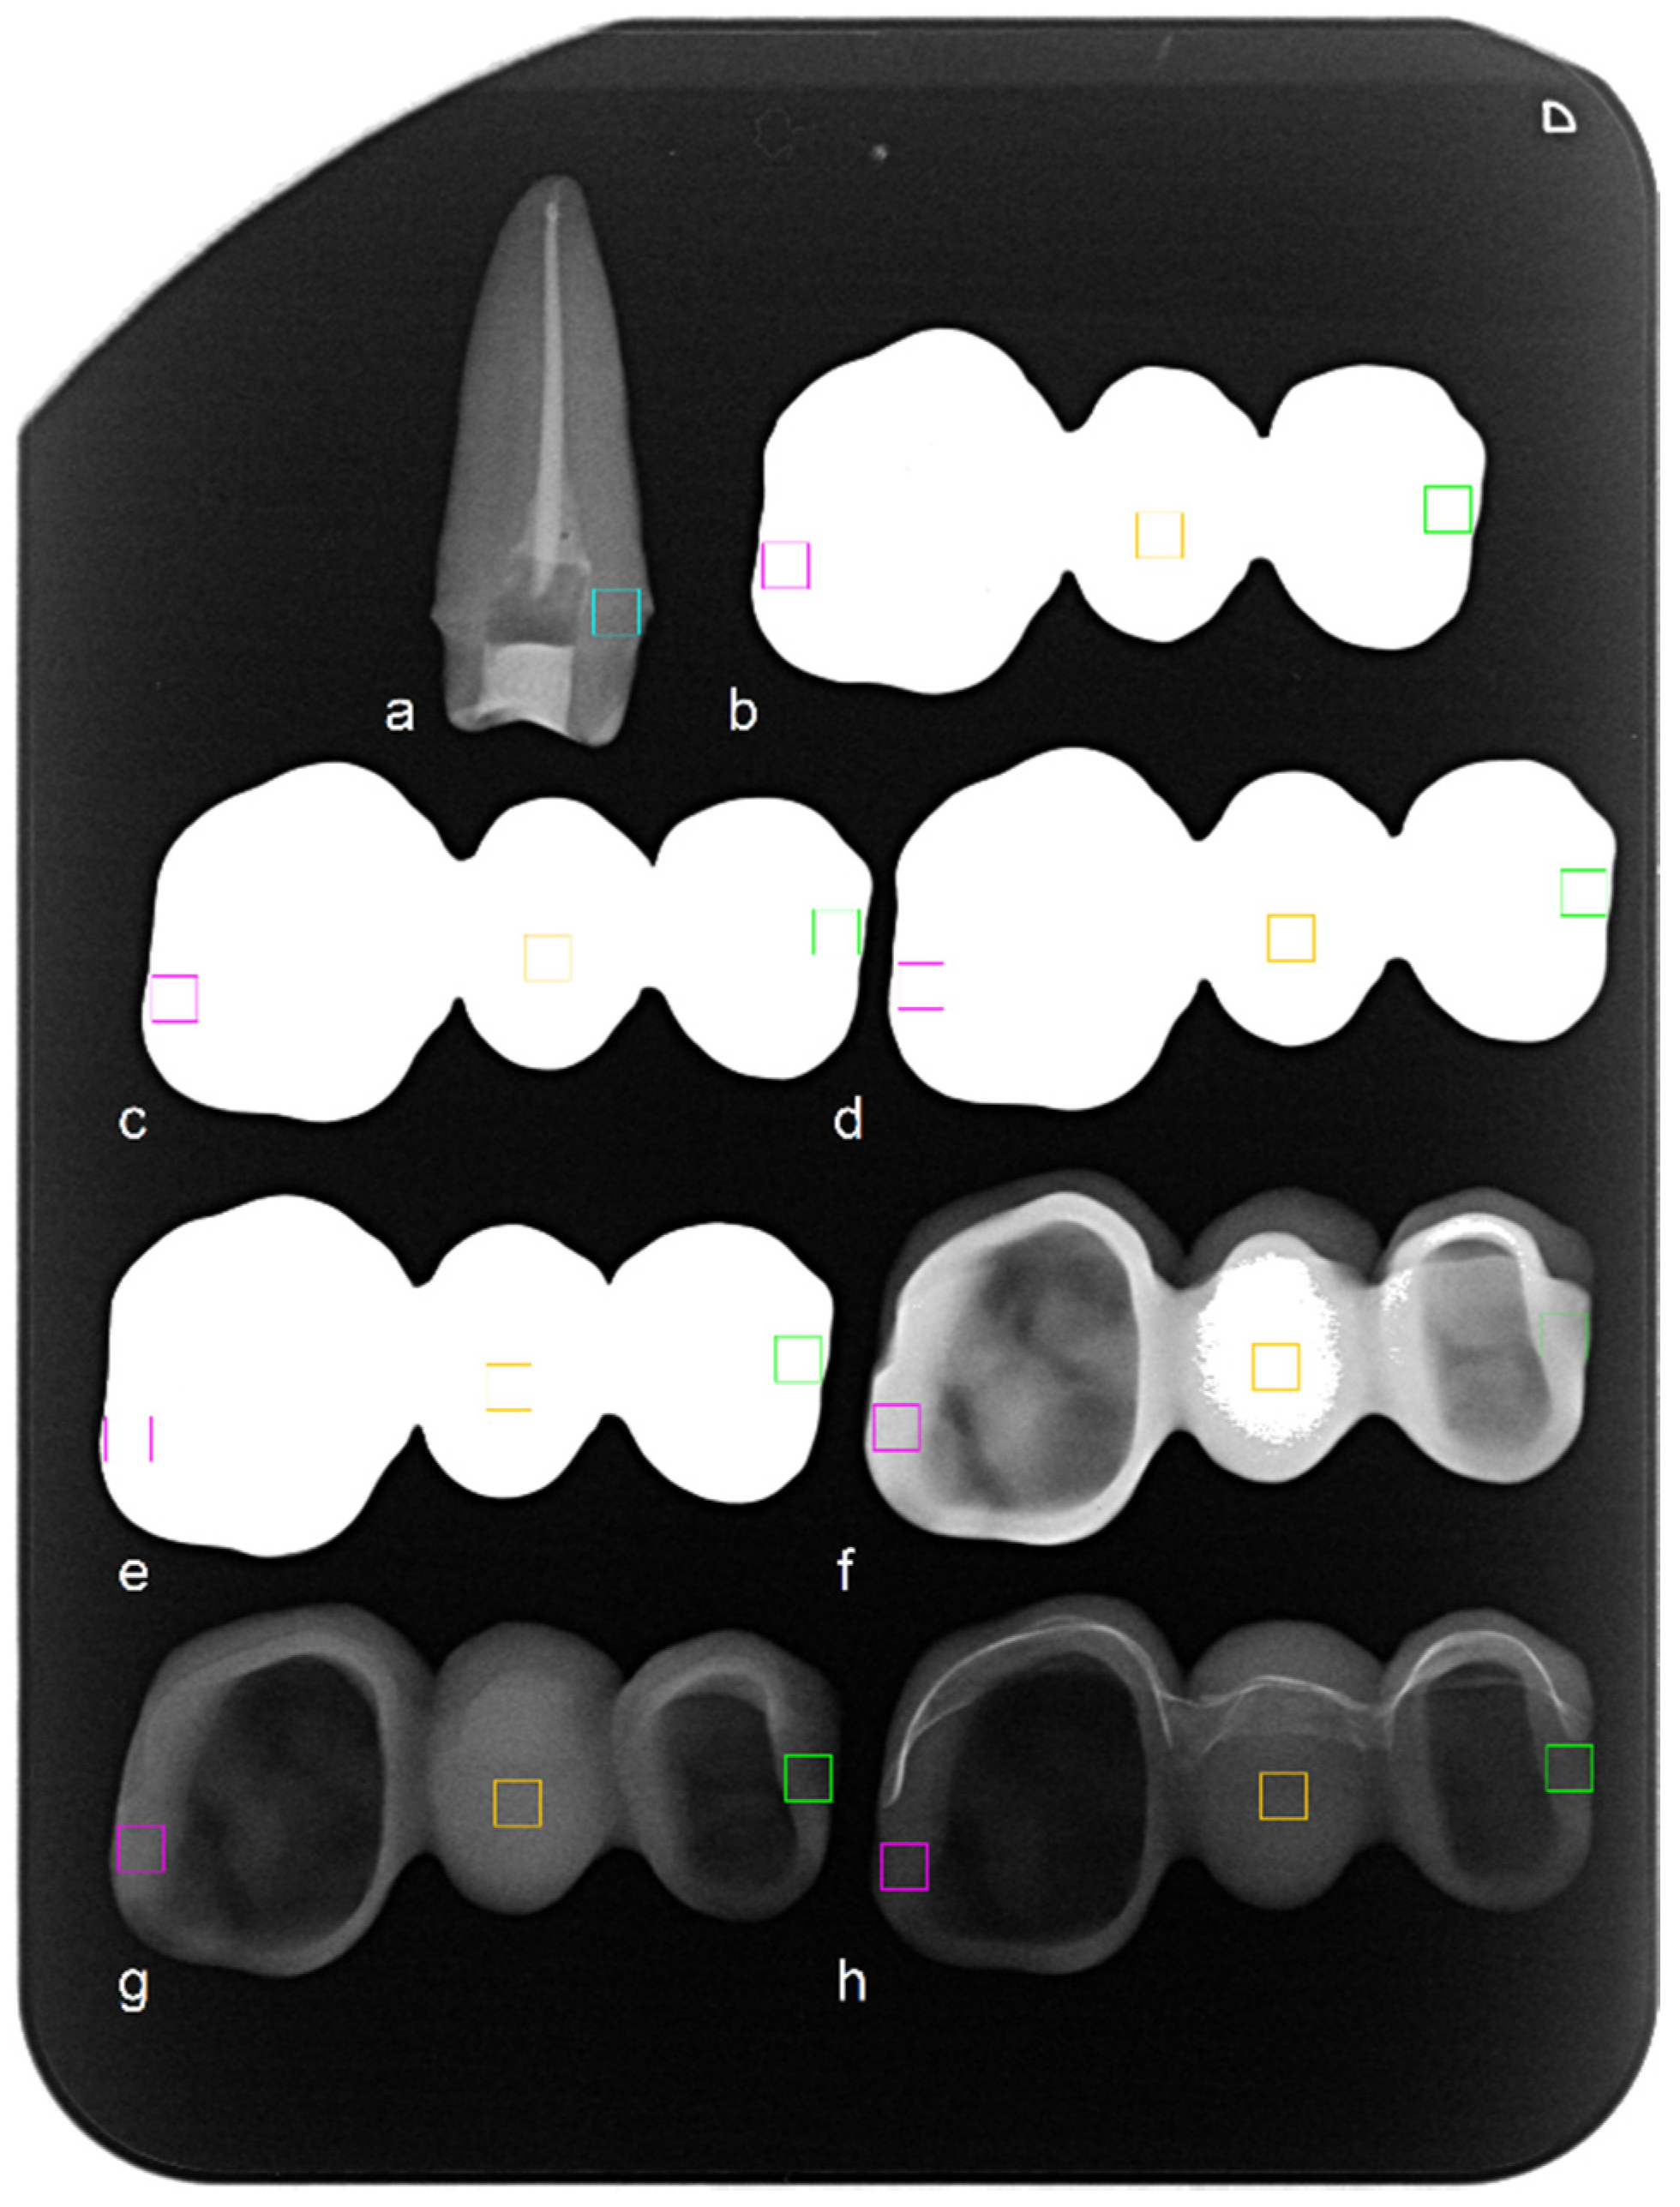

2. Materials and Methods

3. Results

| Mean gray value in X-ray a | |||||||

| Pontic area (orange) | 255 | 255 | 255 | 255 | 255 | 99 | 67 |

| Premolar margin (green) | 255 | 255 | 255 | 255 | 174 | 48 | 62 |

| Molar margin (pink) | 255 | 255 | 255 | 255 | 199 | 95 | 47 |